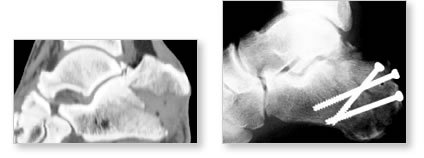

![]() |

|

| This fracture of the calcaneus above has been fixed with screws that have been inserted through skin punctures instead of large skin incisions. |

| The x-ray on the left shows the foot prior to surgery. The x-ray on the right shows the foot after the procedure. Note that the height and shape of the calcaneus have been perfectly restored. |